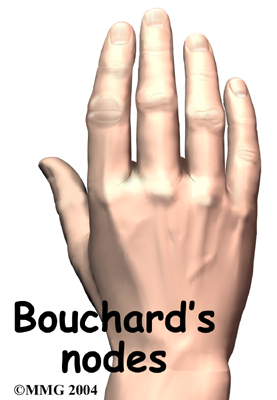

Both forms of arthritis can cause enlarged areas over the back of the PIP joints. These areas tend to be sore and swollen. They are known as .